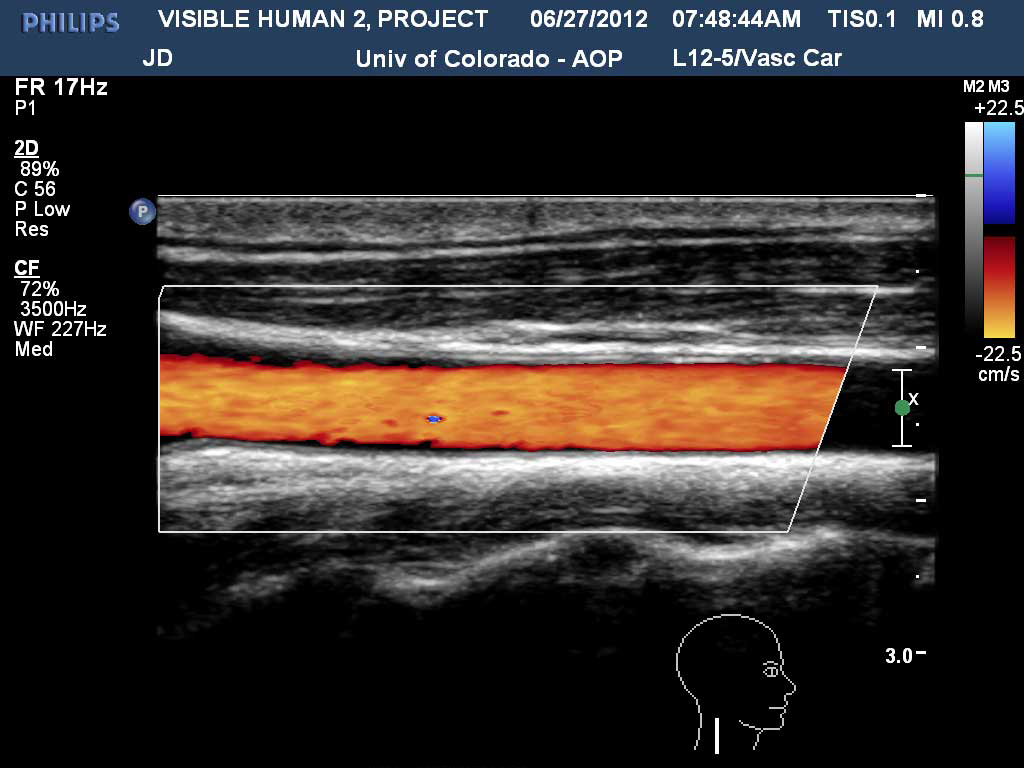

Right Carotid with Doppler